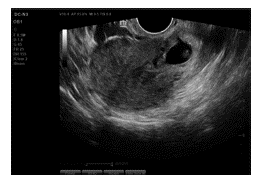

Al examen físico de ingreso, se encuentra paciente en aceptables condiciones generales, normotensa, frecuencia cardiaca con tendencia a la taquicardia, abdomen blando sin signos de irritación peritoneal, al examen ginecológico sin presencia de sangrado activo, sin cambios cervicales. Se deja paciente en observación y se solicitan niveles de gonadotropina coriónica (BhCG), cuyo reporte inicial era de 22162,60 mUI/ml, se revisa lectura de ecografía extrainstitucional, la cual reportaba un embarazo de localización cervical con un saco gestacional de 7 mm. Durante su observación en nuestra institución, se solicita nueva ecografía transvaginal, la cual reporta embrión con longitud cráneo caudal de 7,5 mm, saco gestacional de 20,6 mm y actividad cardiaca de 131 lpm a nivel ístmico izquierdo vs. embarazo en cicatriz uterina (Figura 1).